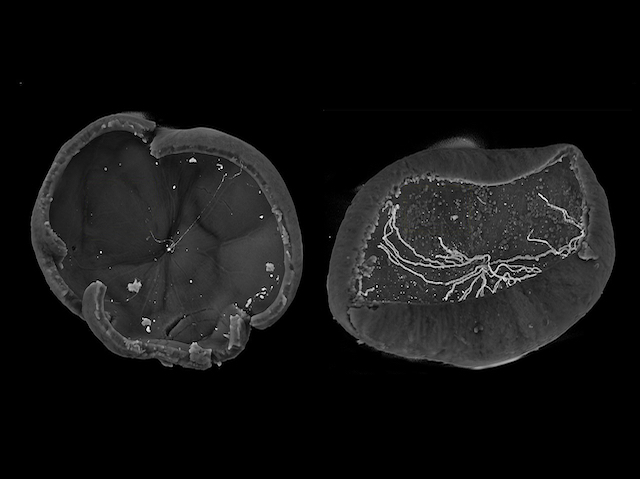

Take an orange, slice its surface, pull it open and squash it flat. Now, could you easily figure out exactly how its insides fit together? Imagine the same problem with the far more complex mammalian eye. When studying eye diseases using traditional microscopy, specimen eyes must be peeled open and flattened, distorting the tissue. Researchers now demonstrate the power of light-sheet fluorescent microscopy (LSFM) for 3D live-imaging whole, spherical mouse eyes. In a mouse model of eye disease, oxygen-induced retinopathy (OIR), LSFM revealed new features previously unappreciated using traditional microscopy. Abnormal blood vessels called tufts, which invade the retina, were found to be knotted. This was confirmed using micro-CT of fixed — and therefore non-living — OIR mouse retina (pictured, right), with lumps of knotted vessels observed pushing through compared to normal mouse retina (left). LSFM could, therefore, reveal new insights in the study of many different eye diseases.